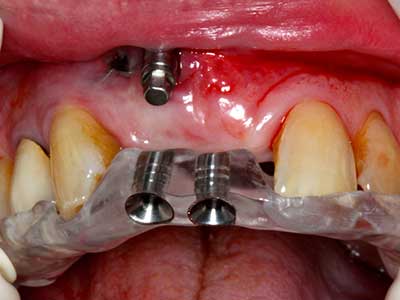

Пиезохирургията има допълнителни предимства при събиране на костни блокове. В допълнение към високата прецизност при остеотомията, описана по-горе, употребата на фините режещи накрайници значително намаляват загубата на материал. Голяма загуба на материал по време на събиране може да се очаква с дебелите накрайници, особено при употреба на борери Линдеман (Lakshmiganthan, Gokulanathan et al. 2012). Базалното разделяне, което е необходимо, особено за присадка на блок при ретромолар, е улеснено от специално създадени правоъгълни триони. В резултат на това, пиезохирургията е разглеждана като прецизна, улеснена и безопасна процедура за събиране на костни блокове в ретромоларното пространство (Happe 2007) (Фиг. 1-12).

Костната тъкан е не само минерализирана структура, тя съдържа и съществено количество колагенови влакна. Това означава, че тя има не само добра компресивна сила, но и известна степен на гъвкавост, която може да се възприеме като предимство при извършване на костна аугментация. В класическата процедура по разширяване чрез костно разделяне, атрофиралият алвеоларен гребен е разделен надлъжно и внимателно разширен след достигане на подходящата остеотомна дълбочина (Фиг. 13-16), в идеалния случай без допълнително отстраняване на периостеума (Brugnami, Caiazzo et al. 2014, Stricker, Fleiner et al. 2014). Системите с винт и пластини с увеличаване на разстоянието при разширяване са доказали ефективността си при разделяне на двете костни ламели, оставайки под прага на фрактурите. В общи линии, оставащата ширина на костта от поне 3–4 mm е задължителна (Chiapasco, Zaniboni et al. 2006), за да се гарантира добра гъвкавост и достатъчно костно покритие за бъдещото поставяне на импланти. Ако е необходимо, вертикалната остеотомия на едната или двете страни може да подобри гъвкавостта. Комбинацията с допълнителни техники за аугментация, особено в букалната страна, е описана като алтернатива на класическата техника.

Процедурата по разделяне е атравматична и няма голяма загуба на пространство, използвайки пиезотриони, и няма значителна разлика между импланти в разделени челюсти и импланти в алвеоларния гребен без костен дефицит (Chiapasco, Zaniboni et al. 2006, Danza, Guidi et al. 2009). Въпреки това, важно е да има достатъчно и продължително охлаждане, особено при ограничено и дълбоко разделяне, за да се избегне термичен стрес в апикално-остеотомните зони.